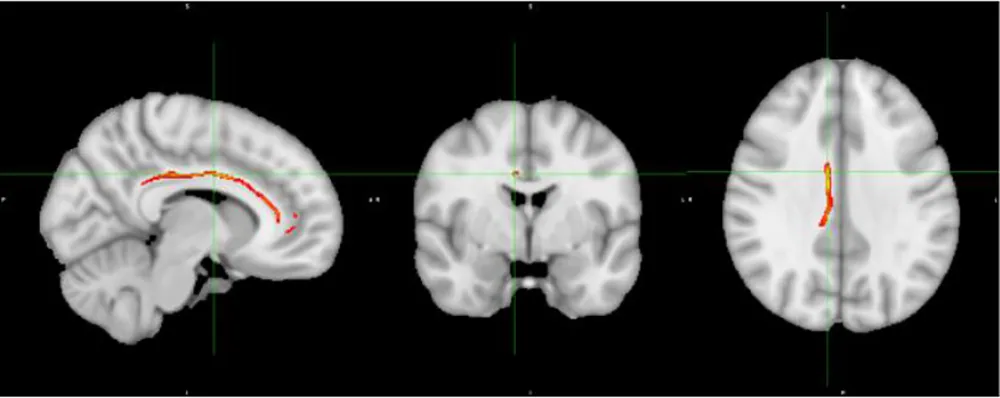

Table 3

| Seed pair for tractography (white matter association tract) | Mean FA | Display |

|---|---|---|

| right IFG-STG (IFOF) | ctl= 0.39 ADHD= 0.41 P=0.09 | ![]() |

| right IFG-posterior cingulate (IFOF, anterior thalamic radiations) | ctl= 0.43 ADHD=0.46 P=0.01 | ![]() |

| right ACC-posterior cingulate (cingulum) | ctl= 0.41 ADHD= 0.44 P=0.08 | ![]() |

| left MTL-posterior cingulate (left SLF) | ctl=0.44 ADHD= 0.47 P=0.024 | ![]() |

Inhibitory network tracts showing fractional anisotropy changes.

Tracts of the inhibitory network with trend differences in FA, Ctl, control.